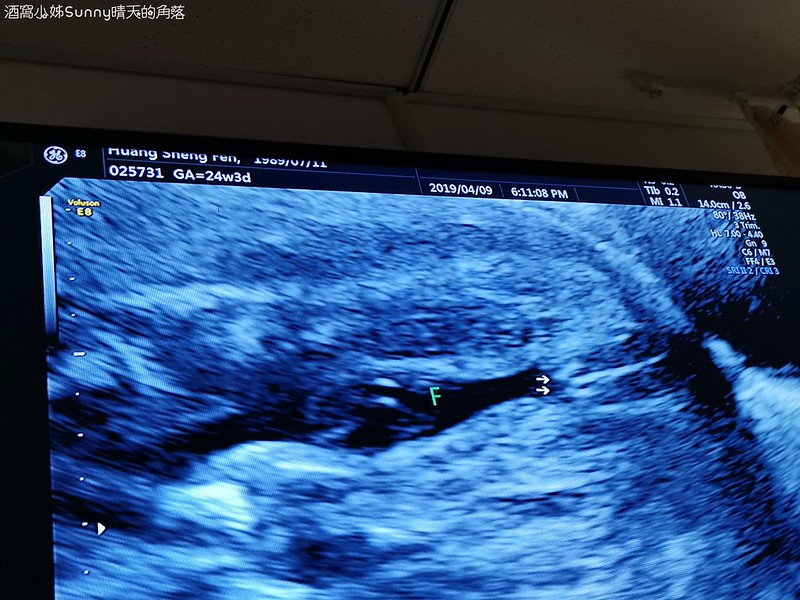

▼這個應該比較好懂!醫生在數寶寶的肋骨一共有12根

▼這個是寶寶的腎臟

下圖你們猜得出來是在看寶寶的甚麼嗎?

▼答案是:外生殖器,也就是性器官,Abby's二寶是「妹妹」唷~